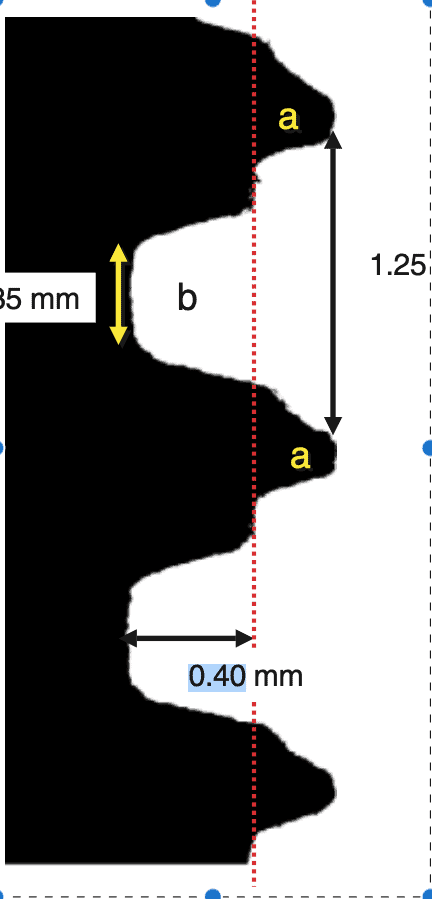

How do implants achieve enough friction to give clinical stability? No rocket science here again, mainstream implants use the two oldest tricks in the book (of mechanics): threads and “wedging”. Threads are typically wider than the osteotomy so that they “bite” in the walls of the osteotomy and stabilize the screw. Wedging means having an implant that is slightly wider than the last drill consequently pressing as a “wedge” the bone walls and increasing in this way the friction. In the past some true wedge-form implants were marketed, such as the Endopore which had no threads and were literally hammered in the osteotomy. They achieved primary stability and osseointegrated, though I am not sure of the success rates. The idea (or the company) eventually died out.

Not only it had very protruding threads, but there was an additional “pitch” at the top of each thread which would have probably made the traditional Straumann users of that time scream in disgust! So this implant never made it to humans, but remained in the notoriously small market of Beagle-dog implants. Nevertheless, this design was genius for the purpose of the experiment, as it created areas of compression (at the pitch of each thread) and areas of no contact, or empty chambers in the surface between two threads.

Right after implant placement, friction stability was achieved thanks to the pitches of the threads biting tight into the bone walls, while the non-contact areas filled with blood clot. The big news came however on the 4th day, when an interesting pattern of bone resorption occurred at the coronal side of the pitch! Why resorption? Obviously the compression of the bone there had killed a zone of bone about 50 μm, which was now being cleared away.

The collective message of these amazing experiments was the while bone is being cleared at the pitch of the thread, new bone is getting created on the implant surface at the no-contact areas! Surface is a significant factor here, with contact osteogenesis being well established at 2 weeks in humans with SLAactive implants, as documented by another great study by Lang et al (4). Lang as well, noted absence of new bone at the pitch of the thread after 1 week, but significant new bone in non-contact areas, where the “jumping” distance between the implant and the bone was short. Again, this message seen somewhat superficially, lead many to believe that the lower and fewer the implant threads, the better the implant would be, reinforcing the anecdotal concept of “aggressive” and “passive” implants. But as you can’t judge a book by its cover, you shouldn’t also judge an implant by its threads! The missing part here was that an implant with few and shallow threads will be unlikely to offer adequate primary stability!

At this point, some might question how do we get primary stability with tissue level implants then, having so few and mild threads? Again, the two oldest tricks in the book: if you don’t make use of the threads you will have to use the wedging, or most likely a combination of both. Indeed, the tissue level implants are 0,6 mm wider than the last drill, which could create a significant bone compression effect, not just gathered at the threads, but most likely spread throughout the whole body of the implant or the most narrow part of the osteotomy. So yes, what many perceived as a definition of a passive implant, might not be that passive after all! Maybe borrowed from psychology “passive aggressive” would be a better term..!

Tapping will reduce insertion torque of the implant, but not the bone compression. Tapping is cutting the shape of the implant in the bone, using a “thread cutter” which has exactly the same dimensions as the implant. This way it clears out the 0.6 mm jumping distance compressing the bone, parts of which will get a plastic deformation as a result. So when the implant comes, the bone is already pushed out of the way with the segments under plastic deformation offering no longer friction, while those under elastic deformation will contribute to stability pushing back on the implant surface. The same will happen if you reverse the implant a few threads and then torque again, as many clinicians will do when the insertion torque gets too high. Taping or tricks such as reversing will reduce insertion torque, but the overall bone compression will be the same.